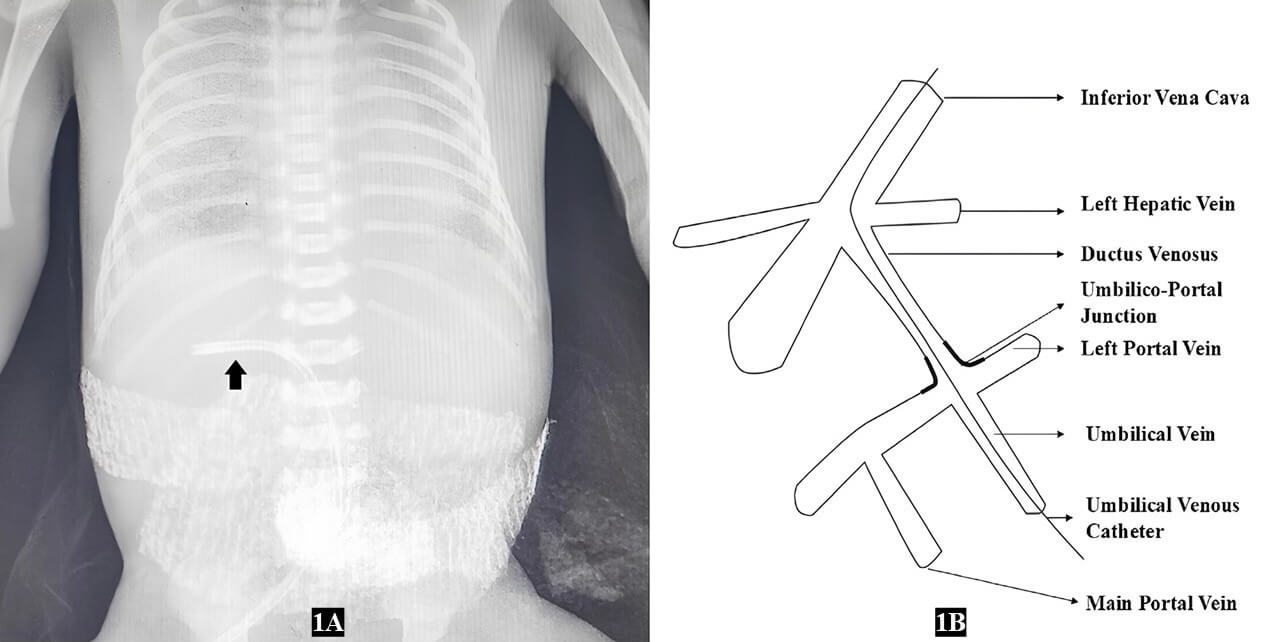

A preterm male neonate, born at 34 weeks of gestation, by emergency cesarean section, with a birth weight of 1.8 kg, presented with severe respiratory distress and required central line placement for intensive care management. An umbilical venous catheter (UVC) was planned, and the insertion length was calculated using Shukla’s formula. The UVC was placed under aseptic precautions with an F4 umbilical catheter. Position was clinically confirmed by free flow of blood in either direction. An abdominal X-ray was obtained to confirm the UVC position, which showed the UVC tip in the left portal vein (Fig 1A). The UVC was promptly removed, and vascular access was secured through a peripheral vein.

Fig 1A X -ray of the neonate with an umbilical venous catheter in the left portal vein (arrow) and Fig 1B Anatomy of umbilical and portal venous communication.

In fetal life, the umbilical vein communicates with the left branch of the portal vein at the umbilico-portal junction and continues as the ductus venosus, which joins the hepatic vein and drains into the inferior vena cava (IVC) (Fig 1B).2 When correctly positioned, a UVC follows this anatomical path: it enters through the umbilicus, traverses the umbilical vein, passes through the ductus venosus, and then enters the hepatic vein, ultimately reaching the inferior vena cava (IVC). A sphincter-like structure is present at the origin of the ductus venosus, and its contractility may be influenced by inotropes and by changes in neonatal blood pressure. These factors may prevent passage of the catheter through the ductus venosus, resulting in misdirection of the UVC into the left portal vein.